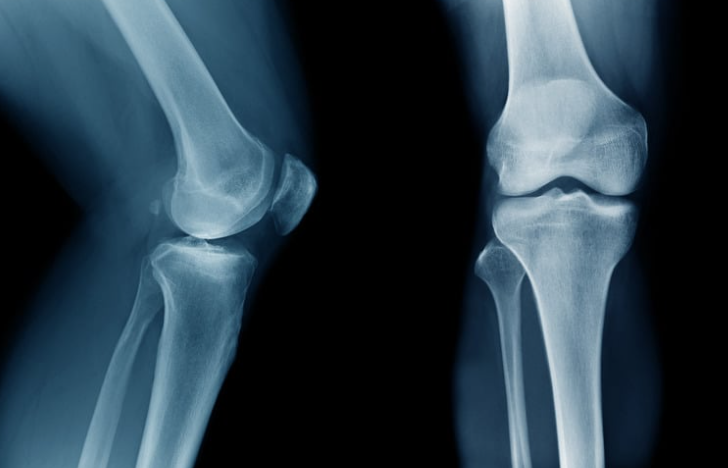

That’s why it hurts far more than a sprain but looks normal on X-ray.

- Knee (most common — especially after sport)

X-rays don’t show bone bruises.

No. They require MRI.